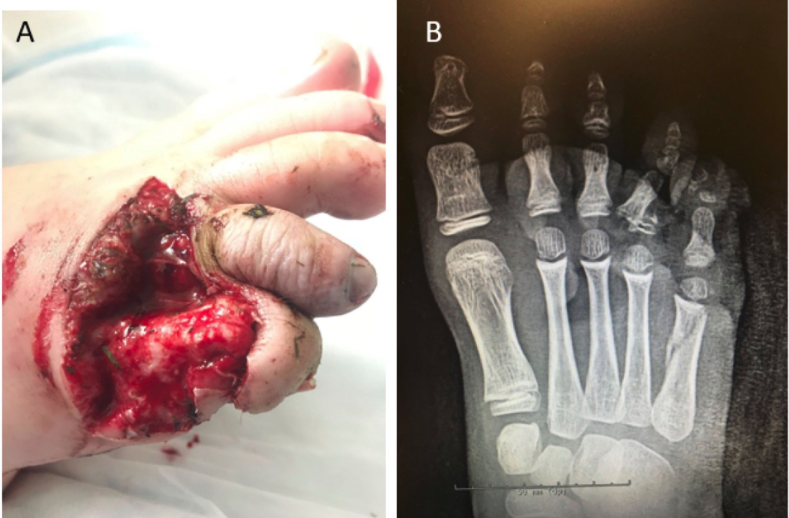

Six (26.1%) patients ultimately received a simple reconstruction (ie, primary closure), 1 (4.3%) underwent a skin graft, 6 (26.1%) underwent a local flap, 2 (8.7%) had a free flap, and 8 (34.8%) required immediate amputation. Examples of the lawnmower injuries encountered and the subsequent reconstructions they received can be seen in Figures 2 through 4.